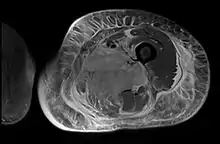

Creatine kinase may be normal or increased probably depending upon the stage of the condition when sampling is undertaken. ESR is elevated. Planar X-ray reveals soft tissue swelling and may potentially show gas within necrotic muscle, Bone scan may show non specific uptake later in the course. CT shows muscle oedema with preserved tissue planes (non-contrast enhancing). MRI is the exam of choice and shows increased signal on T2 weighted images within areas of muscle oedema. Contrast enhancement is helpful but must be weighed against the risk of Nephrogenic Systemic Fibrosis as many diabetics have underlying chronic kidney disease. Arteriography reveals large and medium vessel arteriosclerosis occasionally with dye within the area of tissue infarction. Electromyography shows non specific focal changes.